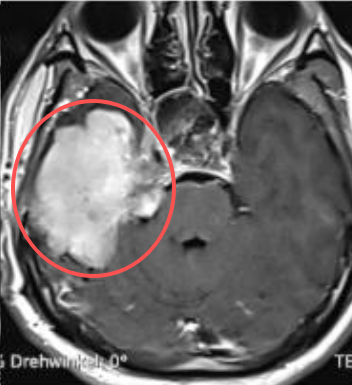

40多岁的林先生早在2012年查出岩斜区脑膜瘤,面对这个仅1级脑膜瘤,治疗之路并不平坦。历经一次开颅,两次伽马刀,右耳失聪、面瘫,肿瘤还是复发弥漫性并侵犯颅底。

由于已经做过伽马刀,多次放疗可能会对大脑造成过大损伤,手术切除率就至关重要。切得越多,复发率也会随之降低。但手术要求术者拥有丰富的颅底手术经验,而这种手术对巴教授来说并无难度,因为他已经进行此类手术超过30年。